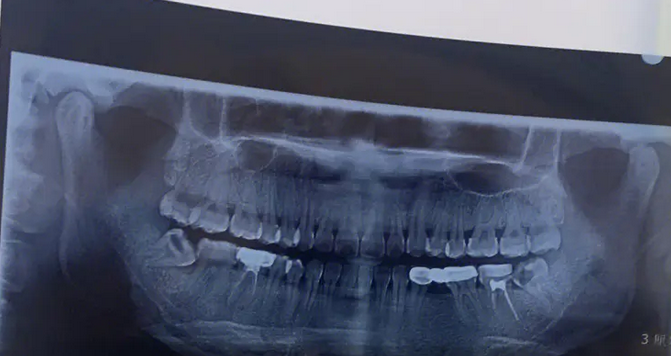

拔智齒之前:

原來我經(jīng)常受到智齒疼痛問題的困擾,為了能夠把智齒拔掉,我在中山大學(xué)腫瘤防治中心的口腔科做了拔智齒的手術(shù)。拔牙前醫(yī)生給我做了檢查,確定了牙齒狀態(tài)。

image.png

拔智齒過程中:

醫(yī)生先給我打了麻藥才拔的智齒,打麻藥后很快就沒感覺了,所以拔牙的過程并沒有很疼,在拔智齒之后醫(yī)生還給我講了很多日??谇蛔o理的注意事項。